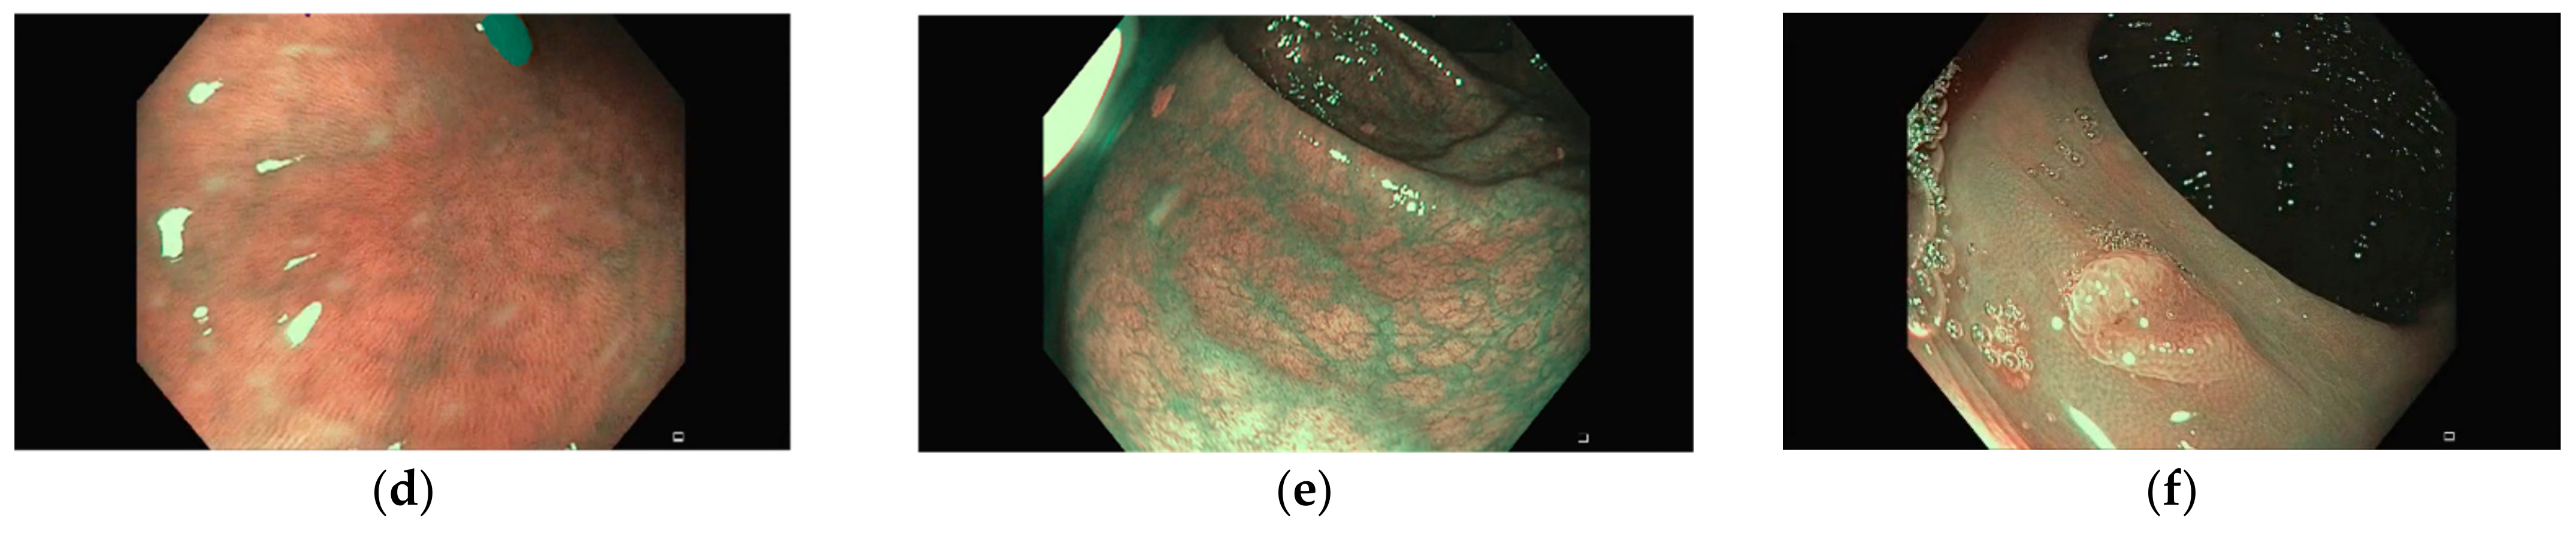

Representative images of the ClinExpPICCOLO dataset are shown in Figure 1. Both WLE and NBI, showing a polyp or not, are included. In comparison to images from the original PICCOLO dataset, images are not focused on the lesions.

Figure 1. Example images. Upper row images (ac) are white light endoscopy (WLE) images, while lower row ones are narrow-band imaging (NBI) images (df). First column (a,d) corresponds to polyp images (lesions are highlighted for better identification), second column shows non-polyp images (b,e) and third column (c,f) are images from the original PICCOLO dataset clearly showing a lesion.